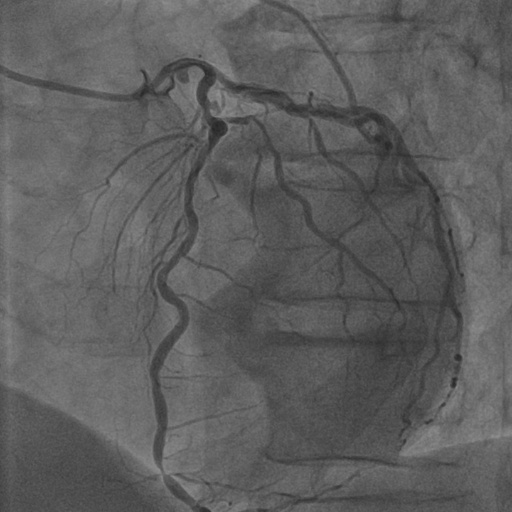

4.1 XACV Dataset

We collect 111 complete records of coronary artery X-ray videos from 59 patients, encompassing the injection, flow through the blood vessels around the heart, and dissipation of the contrast agent. Subsequently, we establish the XACV (X-ray Angiography Coronary Video) dataset. Each video consists of an average of 86 frames of high-resolution coronary artery X-ray images, with an equal distribution of left and right coronary arteries. We invite experienced radiologists to annotate the vascular regions, focusing on one or two frames where the contrast agent is most prominent in each video. These annotations are used only for evaluation in our method, not for training, maintaining the unsupervised nature of our approach. The data collection protocol involves several key steps, including patient preparation with informed consent and metal object removal, image capture using a Philips Allura Xper FD20 machine for standardized frontal (PA) and lateral views, DICOM file storage, and de-identification for patient privacy. Experienced radiologists perform diagnostic annotations using standardized tools and methods, with multiple annotations to enhance accuracy. Quality control measures, secure data management, and strict adherence to ethical guidelines and privacy regulations are implemented throughout the process. The XCAD dataset contains only a single image, and the CADICA video dataset does not provide corresponding ground truth. Therefore, in the following experiments, we conduct all the analyses on our collected XACV dataset and the corresponding GT for each sequence. In Figure 5, we show that compared to other publicly available datasets, XCAD (Ma et al., 2021) and CADICA (Jiménez-Partinen et al., 2024), our dataset exhibits finer annotations in the vascular regions, providing an advantage for future related tasks. The development and use of our dataset have been approved by our institution’s IRB. We will make the XACV dataset publicly available.